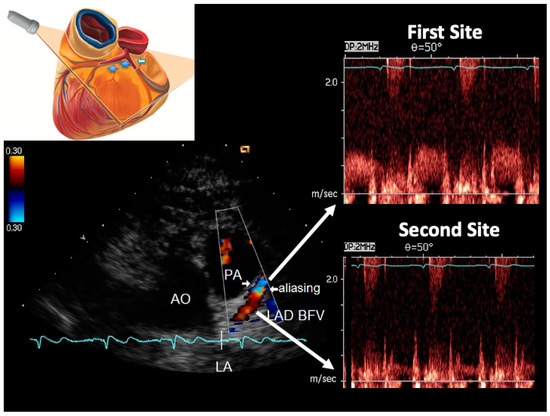

2.2. Color Flow Mapping in the LMA and the Whole LAD

2.4. Ultrasound Plane Orientation

2.7. E-Doppler TTE: Pulsed-Wave Doppler Analysis